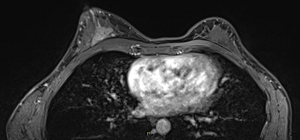

Scans in April revealed the now 34-year-old had aggressive triple negative breast cancer, as well as DCIS (Ductal carcinoma in situ or cancer in the milk ducts).